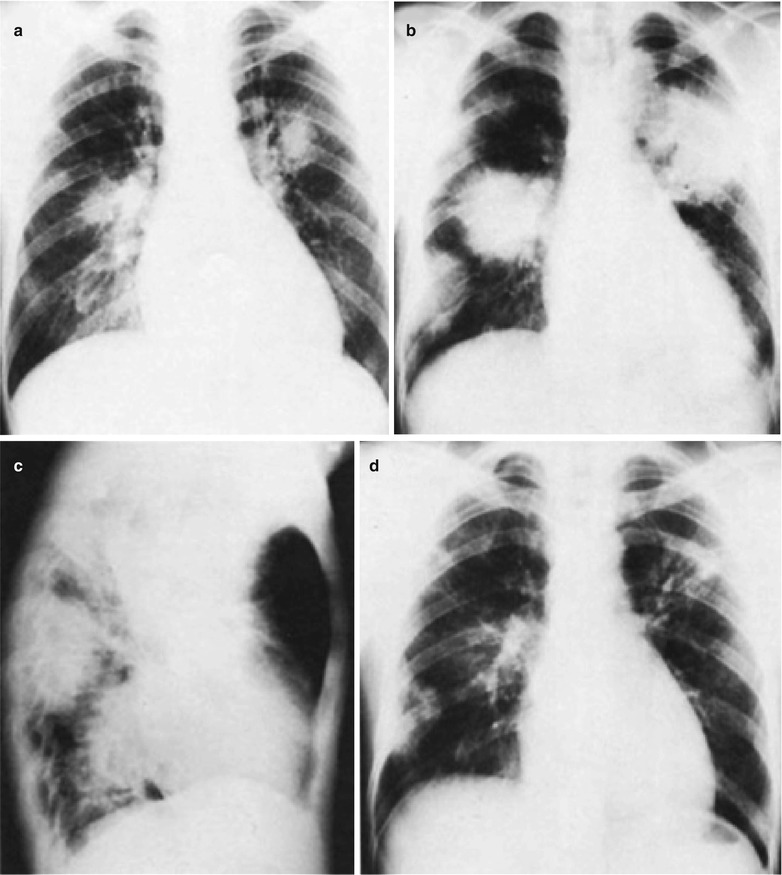

From radiologykey.com

Legionnaires’ Disease Radiology Key Is Legionnaires Disease Pneumonia Legionnaires disease is an atypical pneumonia frequently clinically different from other bacterial pneumonia. Symptoms include high fever, cough, diarrhea and confusion. You can get legionnaires’ disease. The disease got its name when a group of people at an. Legionnaires' disease is a serious type of pneumonia caused by legionella bacteria. Certain people are at increased risk for this infection, but. Is Legionnaires Disease Pneumonia.